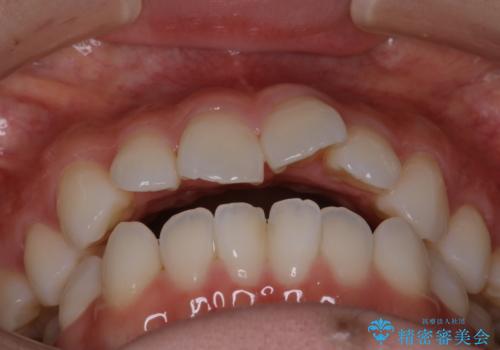

【審美装置】前歯で噛めない!抜歯しないで治したい

- 前歯の捻転とかみ合わせを主訴に来院されました。今回は抜歯をせずにIPRを実施し、並べる計画を立てました。